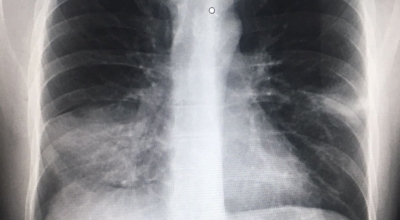

인체가 순조롭게 기능을 발휘하려면 폐 건강이 필수다. 폐는 인체가 효율적으로 움직이는 데 있어 바퀴 안에 있는 톱니 같은 역할을 하기 때문이예요. 산소를 제공하는 폐 기능이 감소하게되면 폐렴이나, 만성 폐쇄성 폐질환(COPD), 천식 등 정도가 심한 호흡기 질환 발생 위험이 증가해요. 이런 질병들은 폐를 공격해 숨쉬기 힘들게 만들어요.

특별히 현대 사회에서 폐는 가장 시달리는 장기 중 한 종류다. 가지가지 공해 성분으로 오염된 공기에 미세 먼지, 황사까지 더하면 폐 안쪽에 있는 허파꽈리(폐포)부터 정도가 심한 훼손을 입습니다. 따라서 폐 건강을 증진시키기 위하여는 폐에 좋은 음식을 섭취할 필요가 있어요.